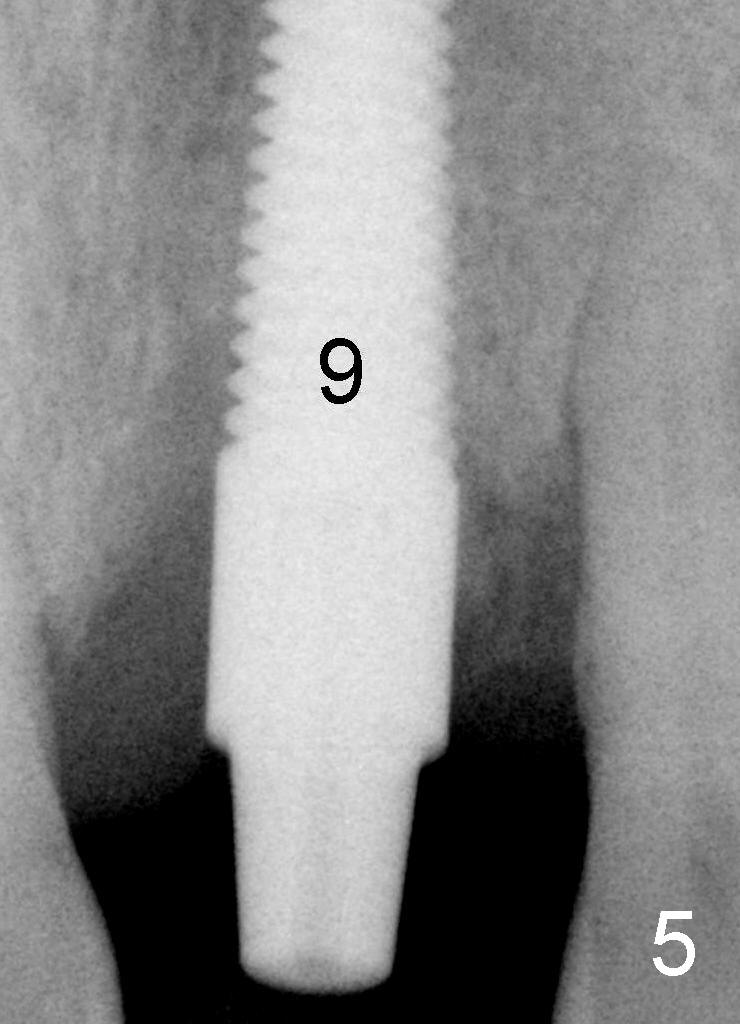

Fig.5 (magnified): Immediately post-implantation: #9: 5x20 mm. Autogenous bone graft from osteotomy (reamers) is to be placed around the implant.